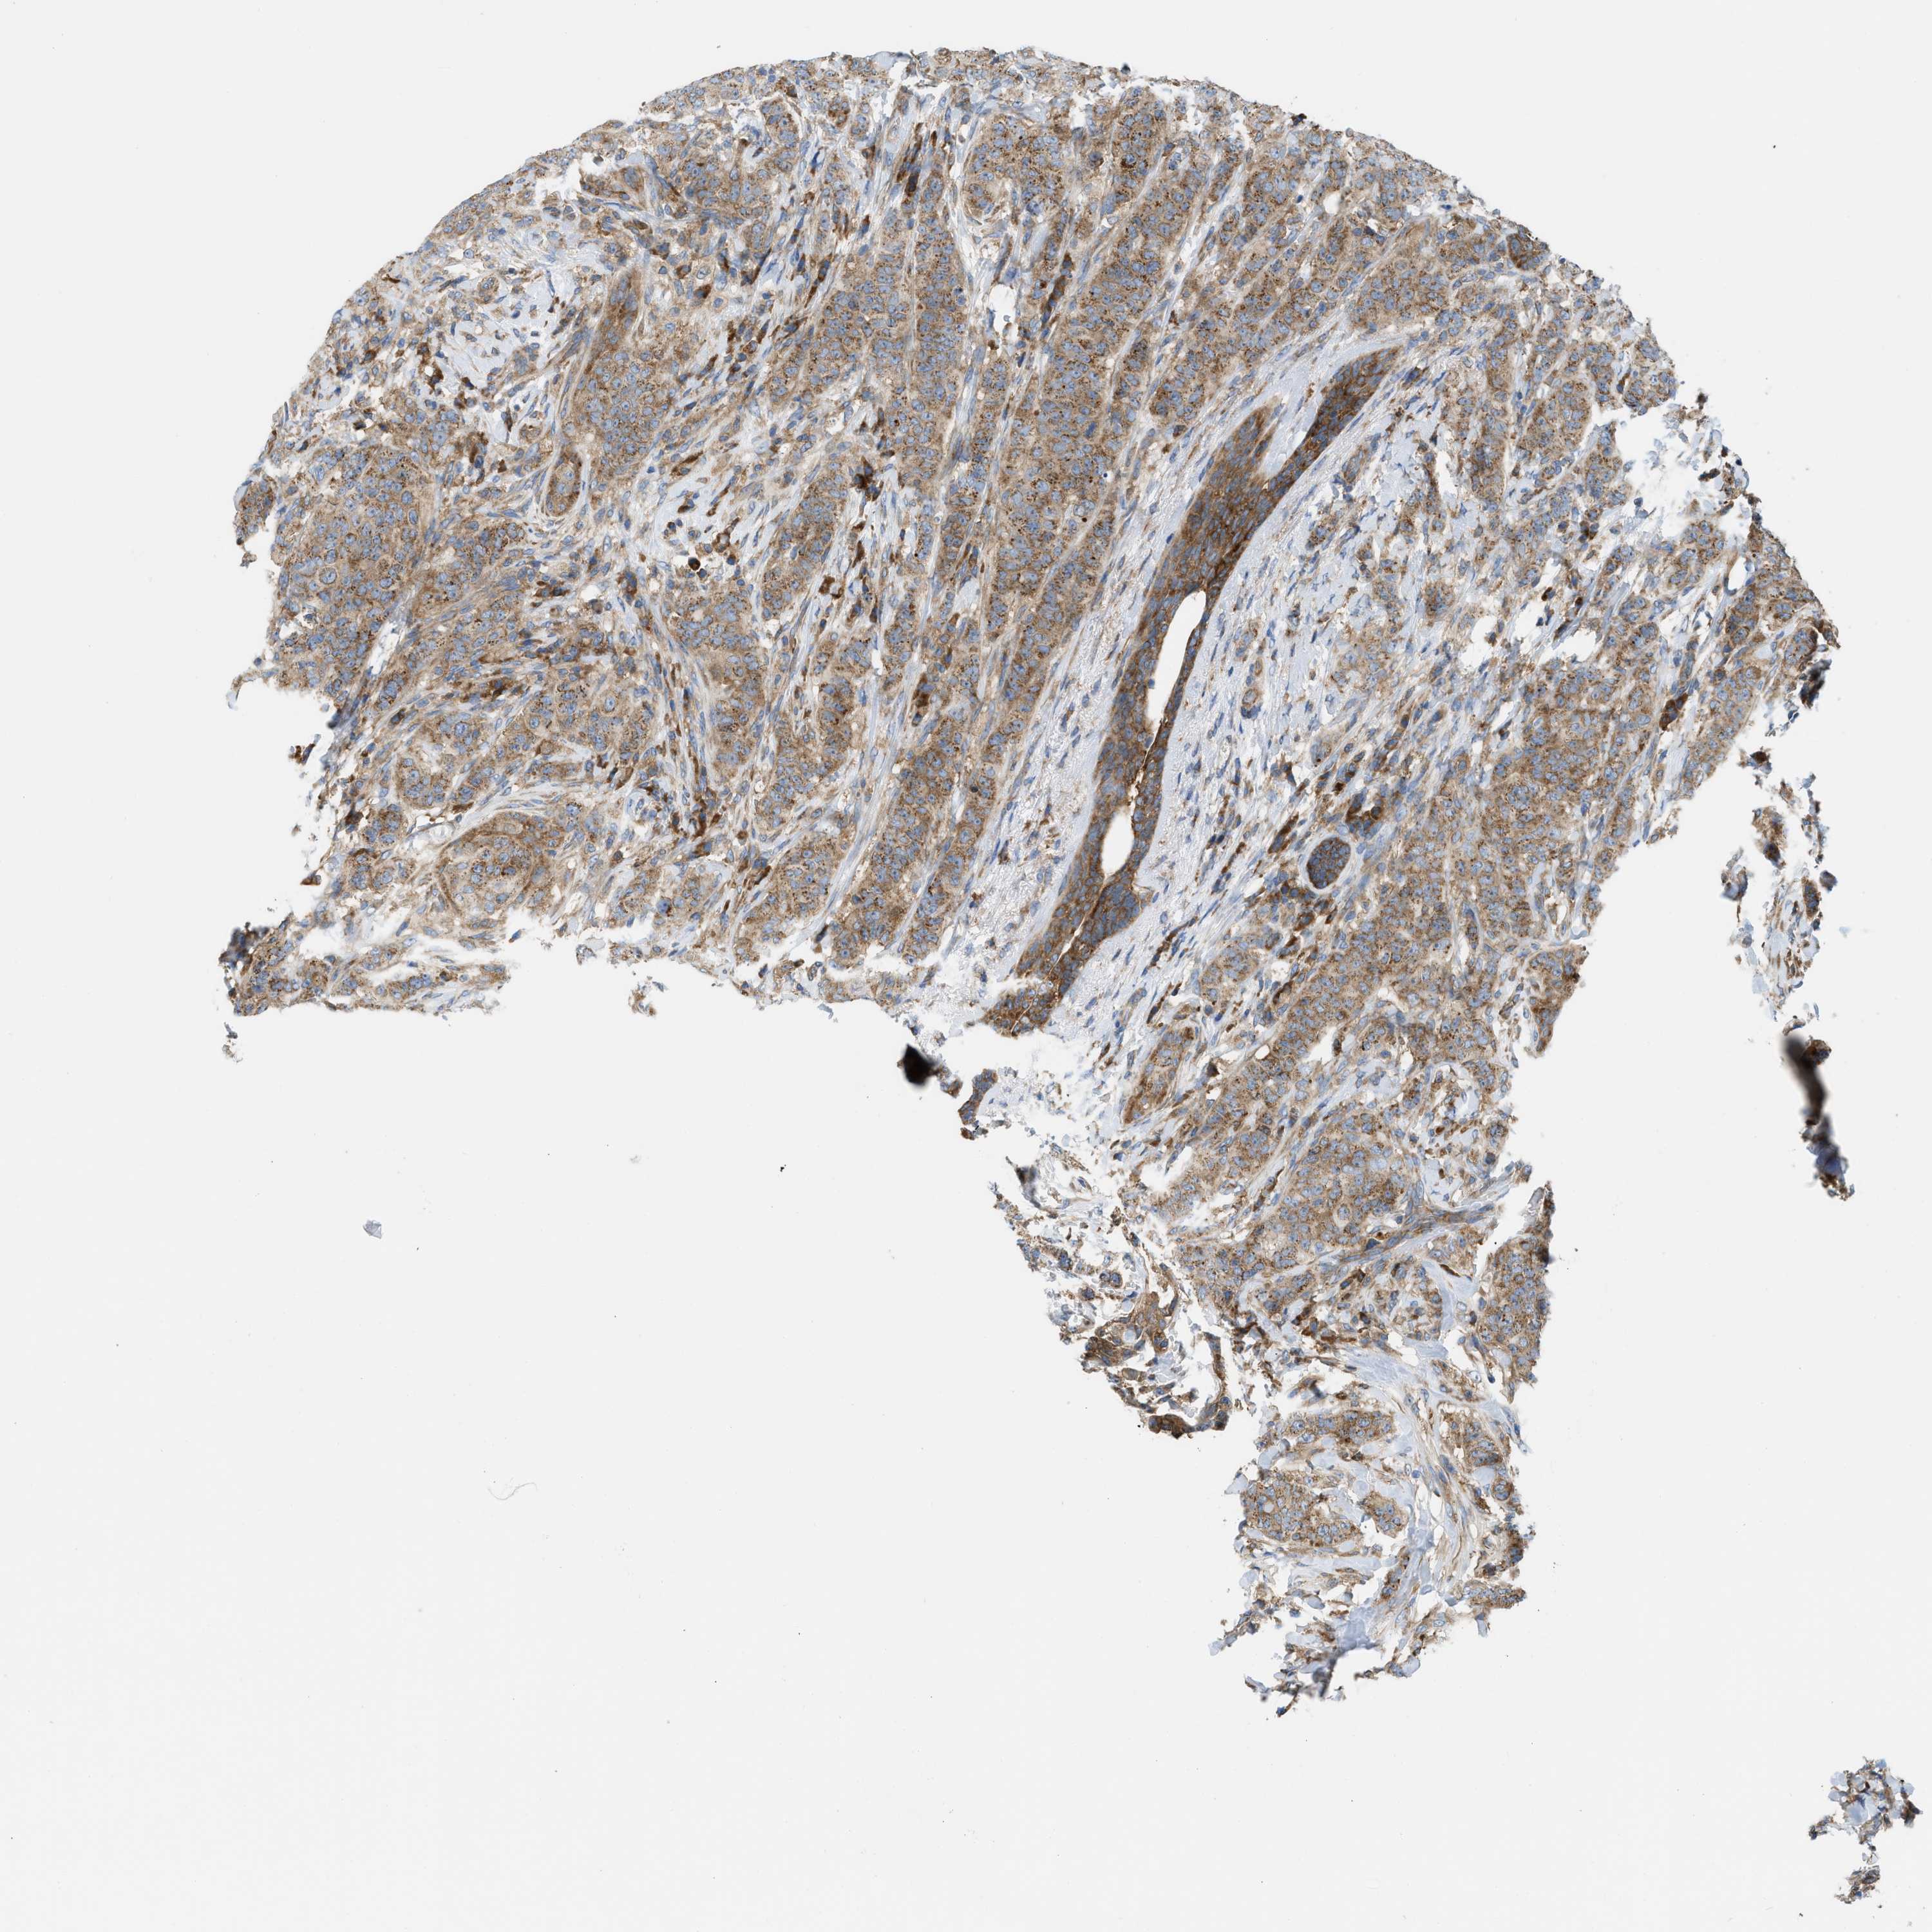

CANCER BREAST CANCER Show tissue menu

BRCA TCGA BRCA VALIDATION PROTEIN EXPRESSION